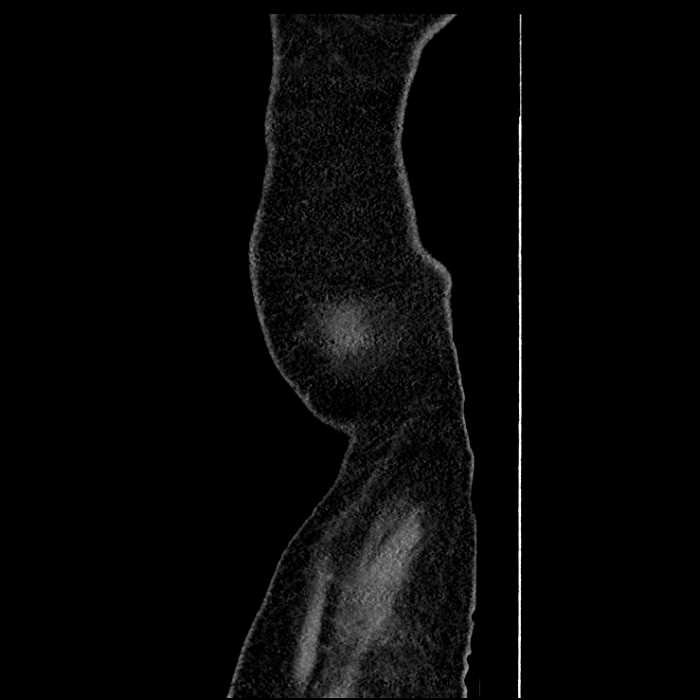

• Large fluid density structure in hepatic segments 7 and 8 measuring 10 x 7 x 7 cm with internal septation and circumferential ill-defined low density compatible with edema

• Peripherally enhancing subcapsular collections along the anterior margin of the left hepatic lobe measuring 3 x 1 cm and 2 x 1 cm

• Clearly marginated fluid density structure in segment 7 and several other scattered tiny hypodensities, which likely represent cysts

Acute sigmoid diverticulitis complicated by a small contained perforation and a large abscess in the right hepatic lobe. Additional small subcapsular abscesses along the anterior margin of the left hepatic lobe.

• The classic CT imaging appearance is a double target sign with internal low density surrounded by an internal enhancing rim (capsule) and a low density external rim (edema)

Hepatic abscess showing the double target sign with low density internally surrounded by a thin inner enhancing rim (red arrow) and ill-defined outer low density rim (yellow arrow). Blue arrow indicates an internal septation. Red arrows: additional smaller subcapsular abscesses. Red arrow: focal contained perforation associated with diverticulitis.